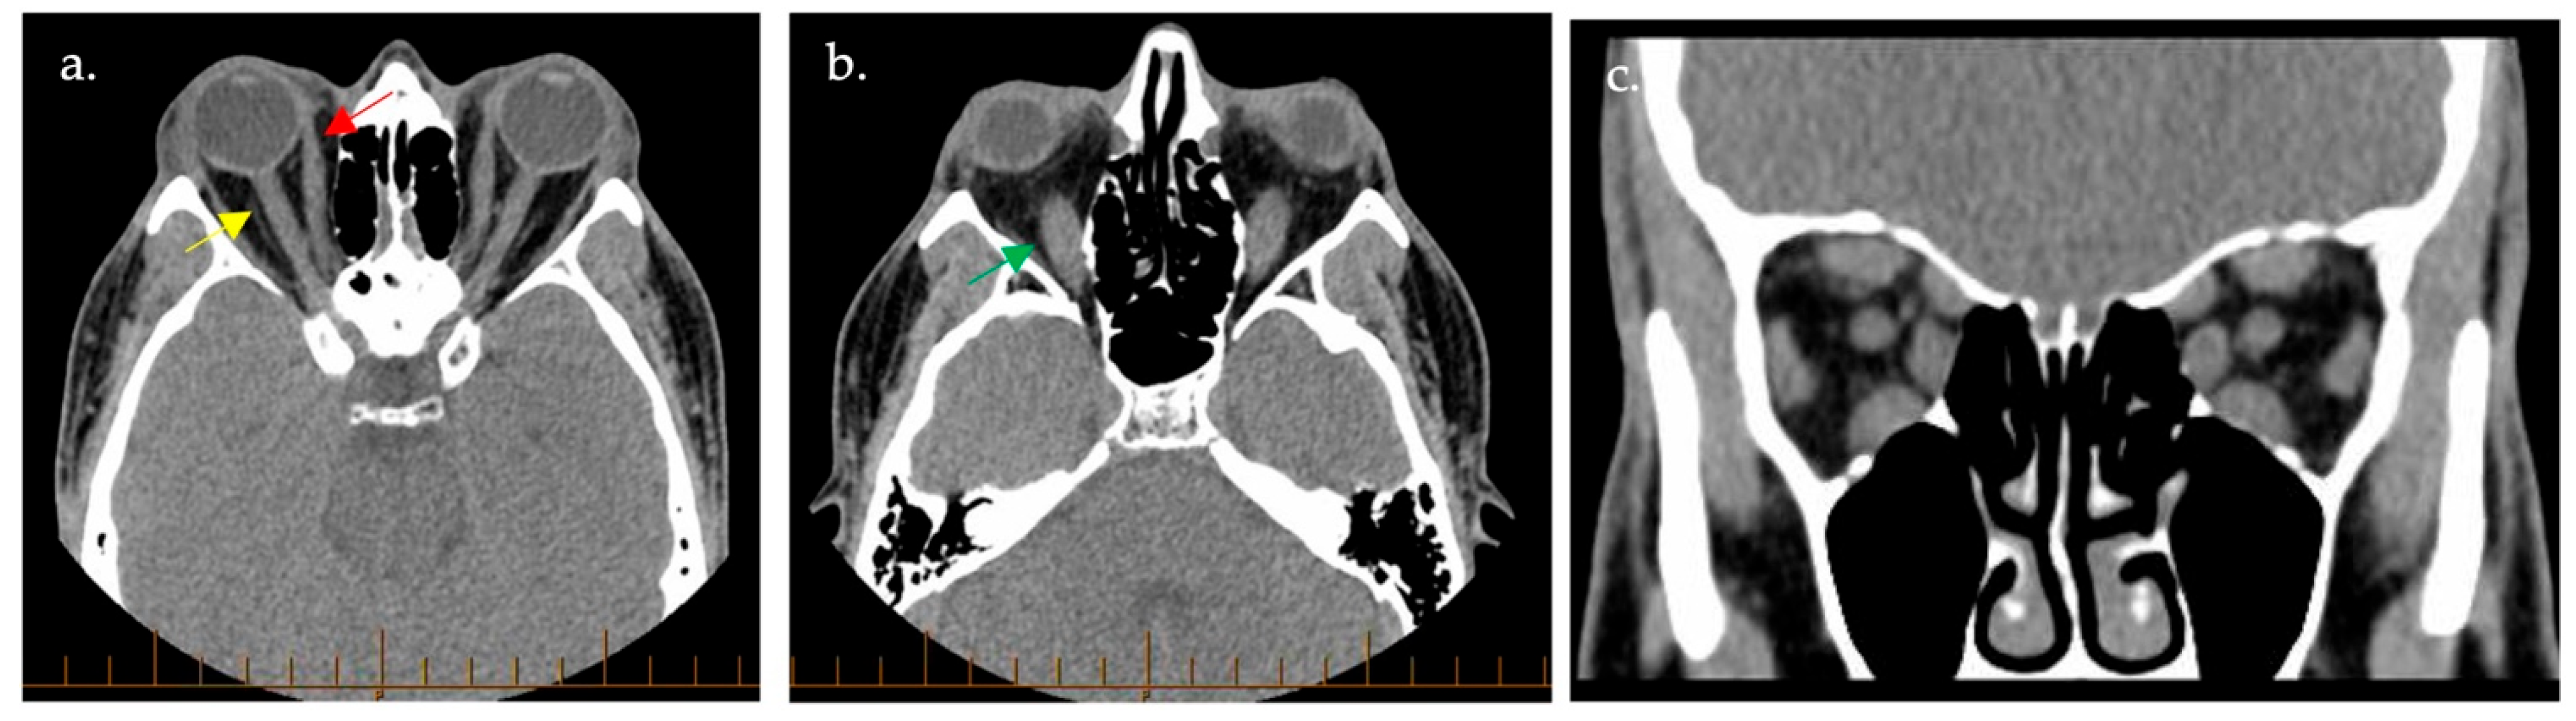

4.3.1. Computed Tomography